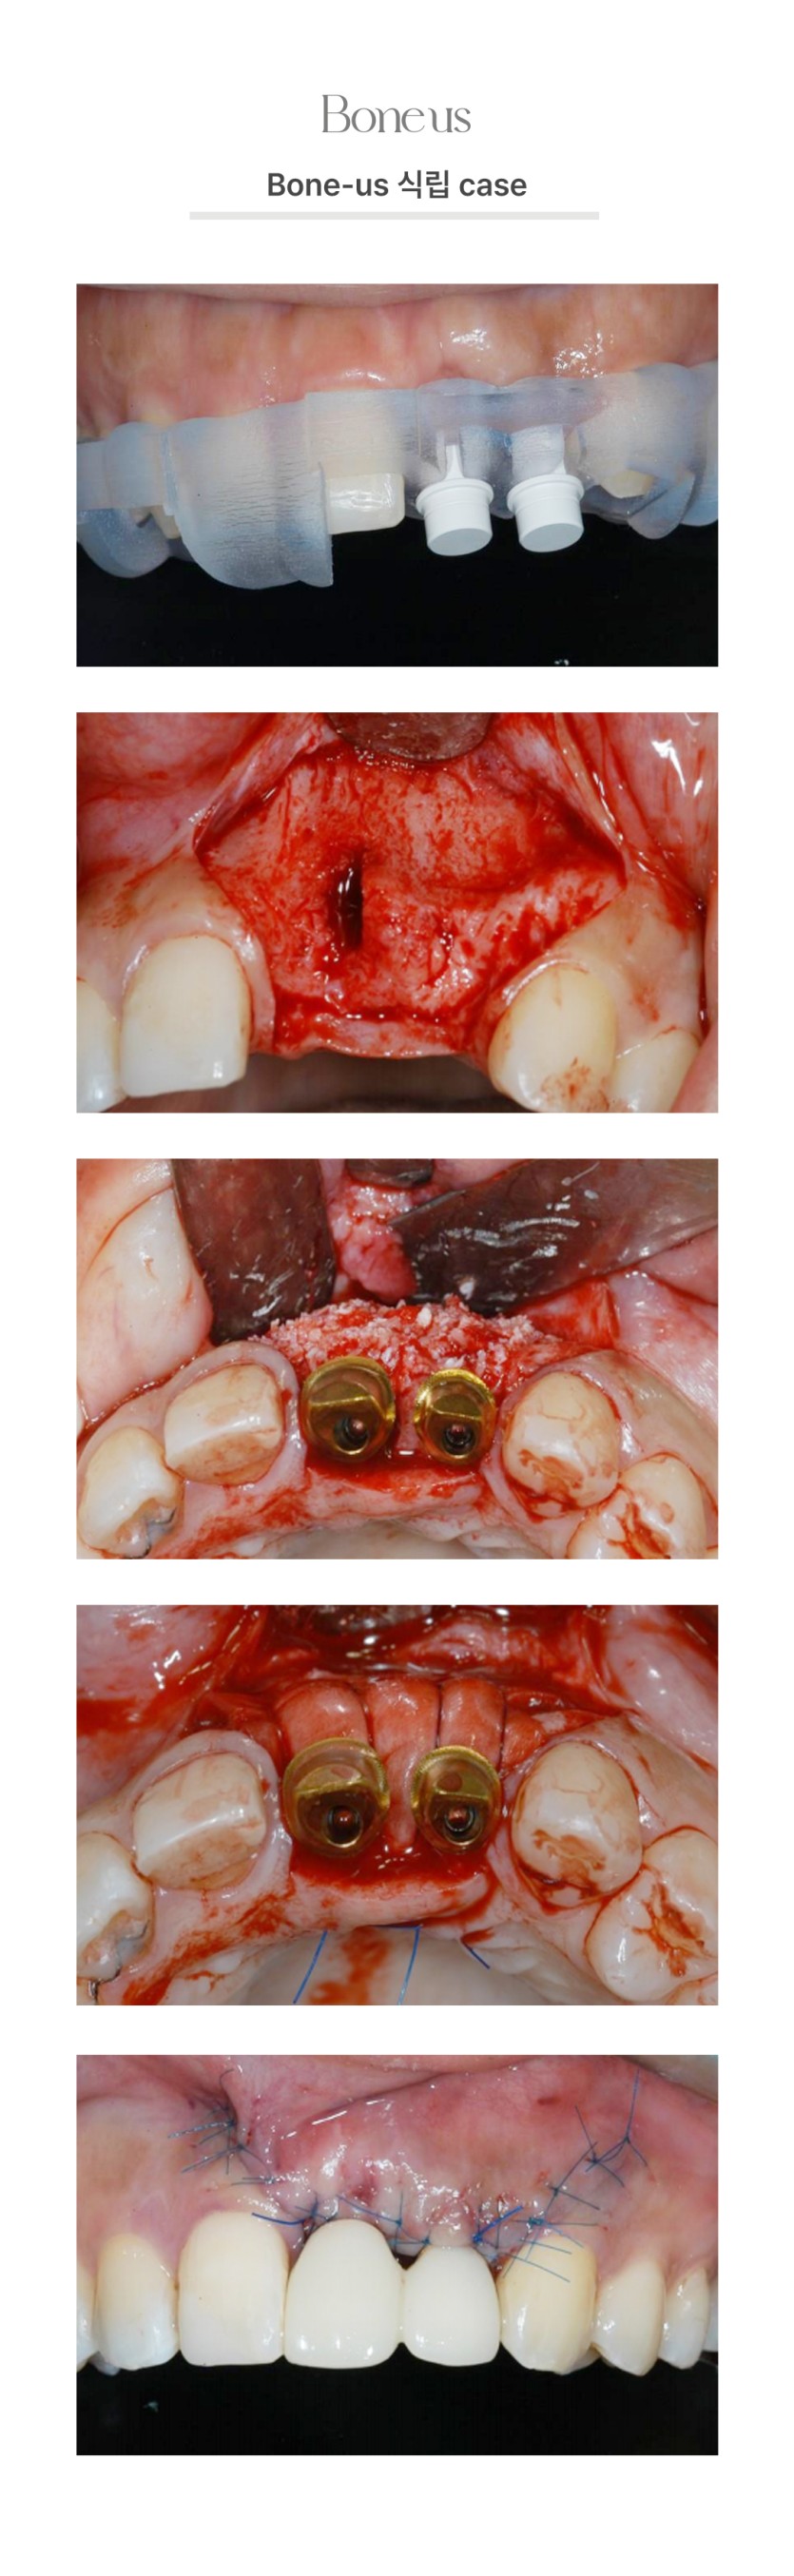

CLINICAL CASE

본어스 시술사례

본어스 식립 케이스 10